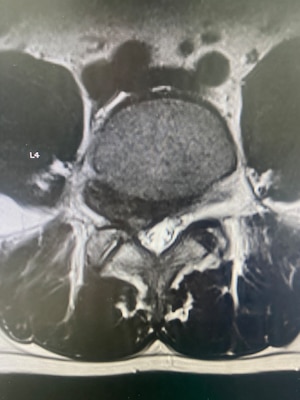

"Uniportal endoscopic spine surgery represents the most minimally invasive technique currently available for treating common spinal conditions such as lumbar disc herniations and foraminal stenosis," Chang explained. "Through a single, small incision, surgeons can access the spine using a high-definition endoscope, minimizing disruption to surrounding muscle, bone, and soft tissue." He said this approach allows for precise decompression of neural elements while preserving normal anatomy.

"One of the greatest advantages of the uniportal technique is its ability to directly target pathology in the foraminal and extraforaminal zones—areas that have traditionally been difficult to access without more invasive exposures," Chang said. "Using a transforaminal or contralateral endoscopic approach, surgeons can visualize and decompress the exiting nerve root along its entire course."